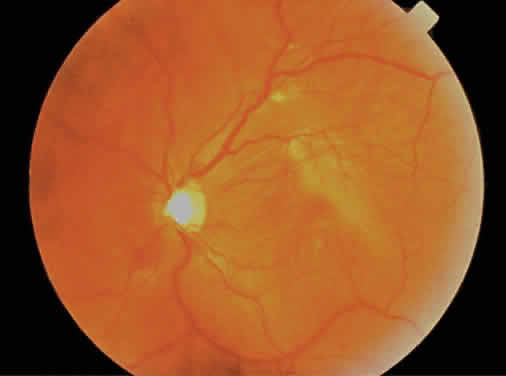

The fundus finding that is most commonly seen with low to moderate degrees of myopia (less than -6 diopters) is a scleral or choroidal crescent located adjacent to the optic nerve head (Fig. 8).26 As the globe expands, the retina, RPE, Bruch's membrane, and choroid are pulled away from the optic nerve head, resulting in the scleral crescent (Fig. 9). In this area, the sclera is clearly visible given the absence of the RPE, Bruch's membrane, and choroid, which are usually found at the temporal aspect of the disc.27,28 In physiologic myopia, its width rarely exceeds one third of a disc diameter. Stenstrom and other investigators29–32 showed that the presence of a peripapillary crescent correlated with increasing axial length but not total refractive power (corneal plus lens power) of the eye.

Fig. 8. Fundus photograph of a pathologically myopic eye. There is diffuse retinal pigment epithelium thinning with increased visualization of the choroidal vasculature, extensive peripapillary atrophy, a lacquer crack extending from the optic disc through the macula, and choroidal neovascularization with subretinal hemorrhage. (Courtesy of Wills Eye Hospital, Philadelphia, PA.)